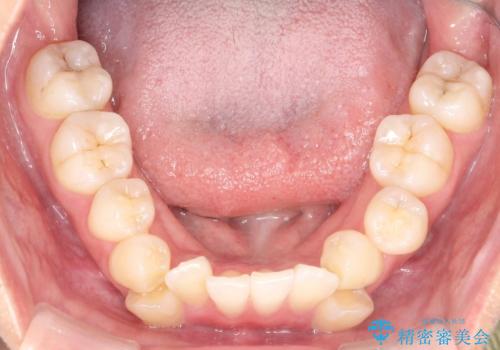

- 「歯のでこぼこを治したい」を主訴に来院された患者様です。 上下ともに、歯のでこぼこが強く、上下左右4の抜歯をし、ワイヤー矯正で治療を行いました。

かなり綺麗に並ぶ事ができ大変満足していただけました。

叢生量がかなり多かったのですが、歯肉退縮も失活歯も無くとても綺麗な歯並びになりました。